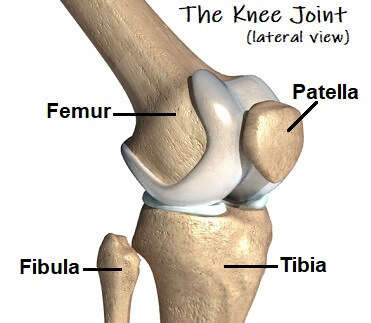

Knee Bones Anatomy Function Injuries Knee Pain Explained shop, Patellar Fractures Broken Kneecap OrthoInfo AAOS shop, Patella Kneecap Anatomy and Function shop, Knee Anatomy Arthritis health shop, The Kneecap Patella and Knee Joint Saint Luke s Health System shop, Patella Wikipedia shop, Knee Joint Function Anatomy shop, Patella the Knee Cap shop, Normal Anatomy of the Knee Joint Middletown Knee Treatment Old shop, Where or Where Has My Patella Gone Direct Orthopedic Care shop, Knee Joint Anatomy and Arthritis SHELBOURNE KNEE CENTER shop, Physiotherapy in Calgary for Knee Pain Bipartite Patella shop, Patella Anatomy function and clinical aspects Kenhub shop, Patellofemoral Pain Syndrome My Family Physio shop, Why You Have a Kneecap and How it Unleashes Your Quads shop, Physiotherapy in Calgary for Knee Pain Bipartite Patella shop, Knee Anatomy Sweep shop, Patella Kneecap Bone Xray Front Anterior Stock Illustration shop, Patella Wikipedia shop, Patella Knee cap Joint surgeon shop, Patella Fracture Broken Knee Cap Orthoriverside shop, Patellofemoral Pain Syndrome OrthoInfo AAOS shop, Knee replacement Understanding your knee shop, Is there something wrong with my kneecap Coastal Orthopedics shop, Has Anyone Dealt With a Knee Cap Bone Spur Training TrainerRoad shop, What You Need to Know About Kneecap Injuries Sports health shop, Knee Trauma Fractures of the Patella Tibial Plateau and Distal shop, Patella or kneecap bone Anatomy bones Leg muscles anatomy shop, Dislocated Kneecap Dislocated Patella for Parents Nemours shop, Kneecap Pain shop, Knee Pain Location Chart SPORT Orthopedics Dallas and Frisco shop, Knee Pain Causes Treatment shop, Why Kneecapping Your Opponent Works shop, Chondromalacia Harvard Health shop, Knee replacement Understanding your knee shop.

Knee Bones Anatomy Function Injuries Knee Pain Explained shop, Patellar Fractures Broken Kneecap OrthoInfo AAOS shop, Patella Kneecap Anatomy and Function shop, Knee Anatomy Arthritis health shop, The Kneecap Patella and Knee Joint Saint Luke s Health System shop, Patella Wikipedia shop, Knee Joint Function Anatomy shop, Patella the Knee Cap shop, Normal Anatomy of the Knee Joint Middletown Knee Treatment Old shop, Where or Where Has My Patella Gone Direct Orthopedic Care shop, Knee Joint Anatomy and Arthritis SHELBOURNE KNEE CENTER shop, Physiotherapy in Calgary for Knee Pain Bipartite Patella shop, Patella Anatomy function and clinical aspects Kenhub shop, Patellofemoral Pain Syndrome My Family Physio shop, Why You Have a Kneecap and How it Unleashes Your Quads shop, Physiotherapy in Calgary for Knee Pain Bipartite Patella shop, Knee Anatomy Sweep shop, Patella Kneecap Bone Xray Front Anterior Stock Illustration shop, Patella Wikipedia shop, Patella Knee cap Joint surgeon shop, Patella Fracture Broken Knee Cap Orthoriverside shop, Patellofemoral Pain Syndrome OrthoInfo AAOS shop, Knee replacement Understanding your knee shop, Is there something wrong with my kneecap Coastal Orthopedics shop, Has Anyone Dealt With a Knee Cap Bone Spur Training TrainerRoad shop, What You Need to Know About Kneecap Injuries Sports health shop, Knee Trauma Fractures of the Patella Tibial Plateau and Distal shop, Patella or kneecap bone Anatomy bones Leg muscles anatomy shop, Dislocated Kneecap Dislocated Patella for Parents Nemours shop, Kneecap Pain shop, Knee Pain Location Chart SPORT Orthopedics Dallas and Frisco shop, Knee Pain Causes Treatment shop, Why Kneecapping Your Opponent Works shop, Chondromalacia Harvard Health shop, Knee replacement Understanding your knee shop.